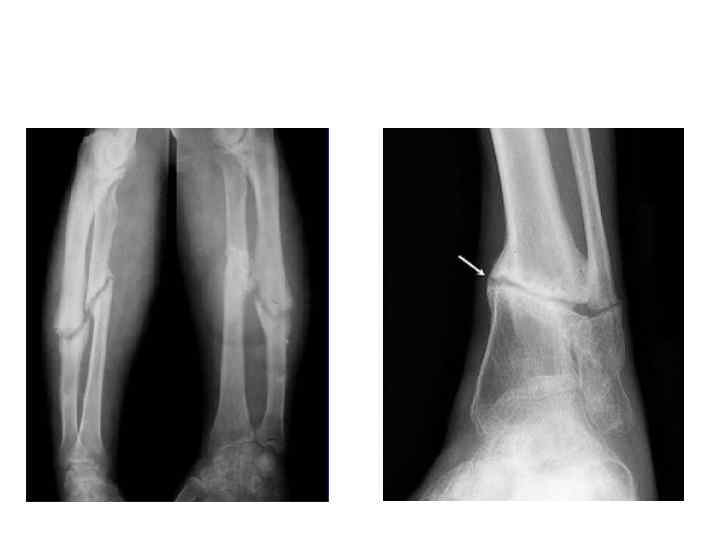

Реконструкция кости при ложном суставе голени

Реконструкция кости при ложном суставе голени – это комплекс хирургических операций, включающих удаление измененных тканей, восстановление правильного положения костных отломков (репозицию), фиксацию поврежденного участка с помощью металлических конструкций (остеосинтез) и, при необходимости, заполнение дефекта костной тканью (костная пластика), чтобы восстановить целостность кости и вернуть функцию конечности.

Операция по реконструкции кости голени при ложном суставе проводится для восстановления нормальной анатомии и функции конечности, так как ложный сустав (неправильное сращение кости после перелома) без хирургического вмешательства не может образовать костную мозоль и срастись самостоятельно.

Цель операции — зафиксировать костные отломки, стимулировать их сращение и устранить болевой синдром и визуальный дефект.